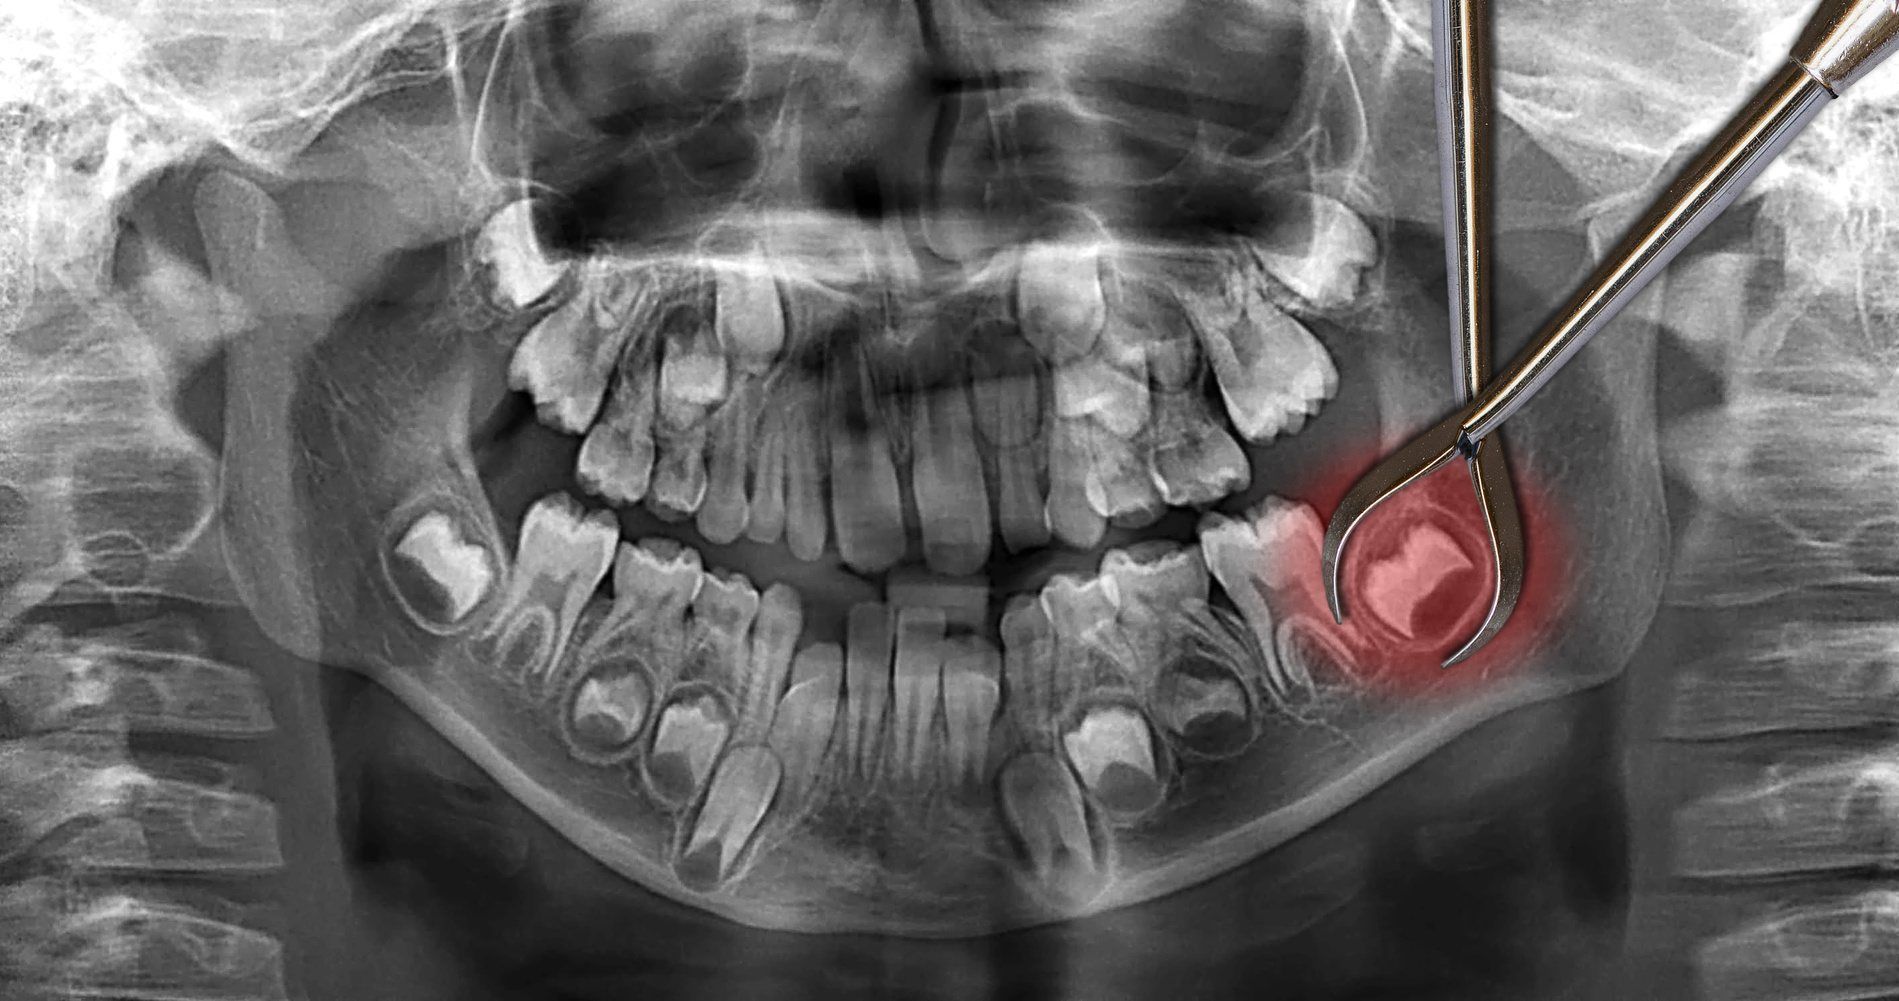

"What's the difference between lateral and crestal sinus lifts?"

Lateral sinus lift approaches from the side of the jawbone and can add significant bone height (5-15mm). It's used for multiple implants or severe bone deficiency. Crestal sinus lift goes through the implant site and adds modest height (3-5mm). It's less invasive but suitable only for single implants with mild bone deficiency.